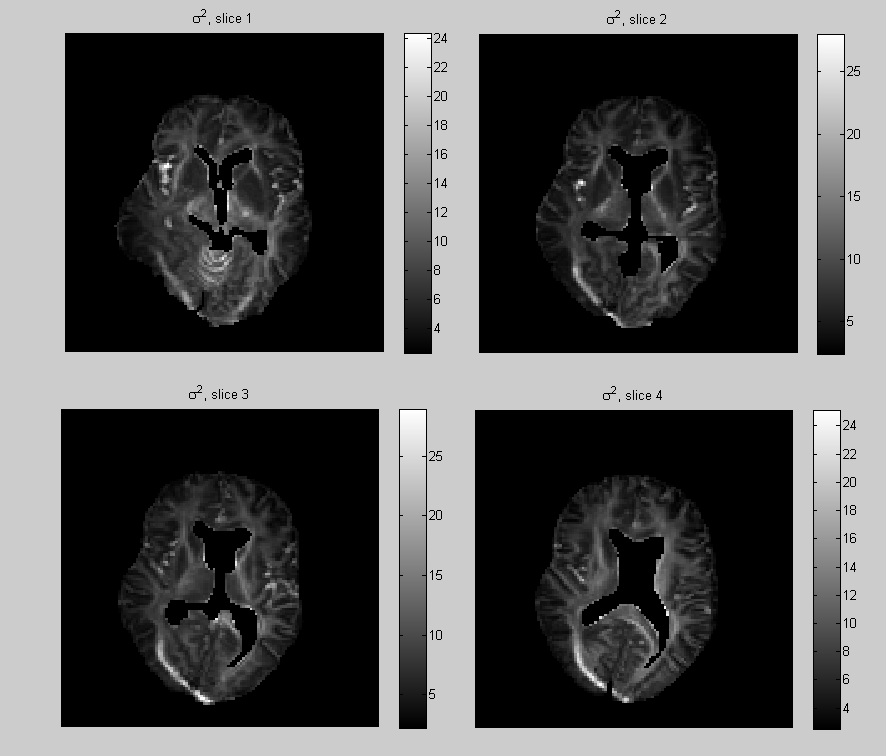

This allows for model comparisons, lower DIC meaning a better fit to the data relatively to the effective number of parameters. In Fig. 6 the DIC is computed independently at each voxel under the 2nd and 4th-order tensor models (without regularization). Note that the voxels with the highest DIC corresponds to artefacts where the data is corrupted, and the area of high DIC correspond to complex white matter structures. We also calculated the overall DIC for all voxel under the model 2nd and 4th-order tensor models with regularization. The respective values DIC and DIC, indicate that when we penalize the model by the effective number of parameters, overall the 2th-order tensor model fits our data better than the 4th-order model. In Fig. 7 the posterior expectation of the noise parameters , are shown. When these are interpreted as residual variances in model fitting, we see that they are consistent with the DIC.